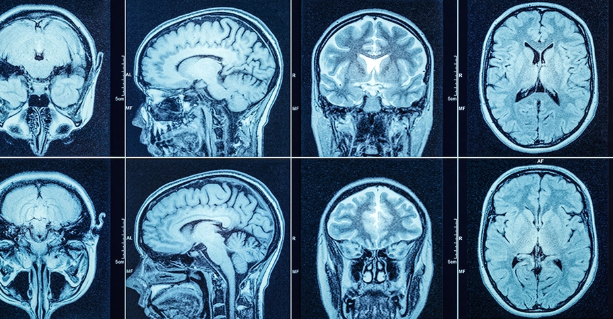

머리 CT 검사는 여러 상황에서 필요하다는 진단이 내려지곤 합니다. 일반적으로 의사가 이 검사를 권유하는 데는 다음과 같은 증상이 있을 수 있습니다.

CT는 일반 촬영과 조영제를 활용한 촬영으로 나뉘며, 조영제를 사용하는 경우 비용이 상승합니다. 조영제는 혈관을 통해 뇌의 혈류 흐름 등을 더 정밀하게 확인하기 위해 사용됩니다.